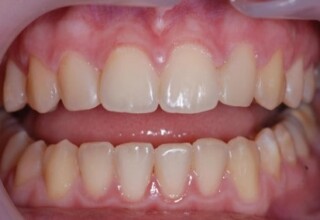

Composite Resin Veneers

Resin veneers are an inexpensive mode of esthetic improvement of anterior teeth, premolars also. Their potential is admirable and their limit is the operator’s clinical dexterity and imagination. In this case there were multiple problems with the upper four incisors: staining, poor inclinations, diastemas, multishading, poor interrelationship and poor tooth-gingiva ratios. They were restored with four direct composite resin veneers (one on a porcelain implant crown!) which were manufactured intraorally!!!